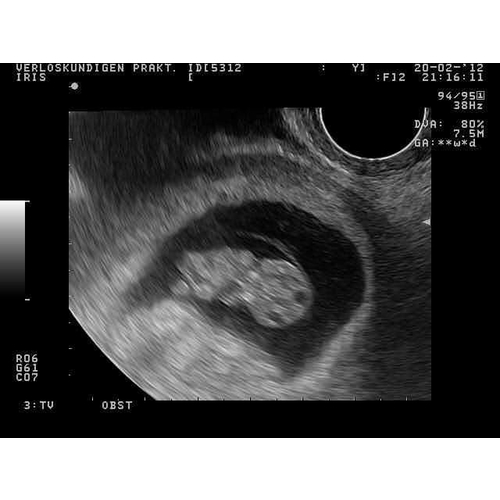

8 weken inwendige echo 馃槉 ben benieuwd